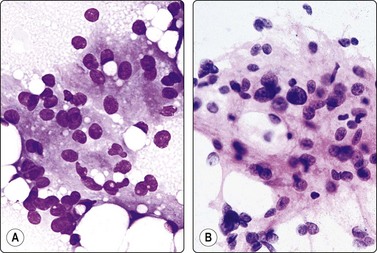

Pheochromocytoma (Figs 12.36, 12.37)128-131

image

Fig. 12.36 Phaeochromocytoma

Loosely clustered cells with prominent anisokaryosis; nuclear chromatin uniformly granular; some large nucleoli; fragile, finely granular cytoplasm (MGG, HP).

Fig. 12.37 Phaeochromocytoma

Mainly dispersed cells, rounded or spindled; anisokaryosis; bland chromatin, abundant fragile cytoplasm with anastomosing strands (A, MGG; B, Pap, IP).

Criteria for diagnosis

Bloody smears, variable cellularity, poor cell cohesion, often vascular components,

Abundant, pale syncytial cytoplasm with anastomosing strands and indistinct cell borders form a web-like background to nuclei; fine red granulation in some of the cells,

Loosely formed acinar or trabecular patterns; linear or curved rows of nuclei,

Striking anisokaryosis of neuroendocrine type: single very large, often spindle or bizarre nuclei or binucleate cells scattered in a relatively uniform population,

Relatively uniform nuclear chromatin; may be coarse, ‘speckled’,

Nucleoli inconspicuous to prominent,

Neuroendocrine markers (NSE, chromogranin A, synaptophysin, CD56) positive; S-100 highlights the sustentacular cells; cytokeratin usually negative.

Needle biopsy of suspected pheochromocytoma is generally discouraged in view of the risk of precipitating a hypertensive crisis, but is not an absolute contraindication if necessary precautions are taken. In any case, since pheochromocytoma may be an unexpected finding and may occur in extra-adrenal sites, the cytopathologist must be familiar with its cytological pattern.

Page 332

Smears are usually bloody but relatively cellular. Cells are poorly cohesive but may be arranged in a loosely acinar or trabecular pattern, or in semicircular rows, and associated with vascular elements. The cytoplasm is abundant and fragile, syncytial, without distinct cell borders, often with anastomosing strands creating a web-like background. There is a fine, red cytoplasmic granulation (MGG) in a proportion of cells. Nuclei vary in size and shape, round, oval or often spindled, sometimes bizarre. Anisokaryosis is typically prominent, seen as scattered very large nuclei in an otherwise relatively uniform population. Bi- or multinucleated cells are common. Nuclear chromatin is granular, evenly distributed and relatively uniform. Nucleoli are inconspicuous to prominent, single or multiple. Intranuclear inclusions are not uncommon, and intracytoplasmic hyaline globules (H&E) are found in some cases.

The pattern closely resembles that of medullary carcinoma of the thyroid, non-chromaffin paraganglioma and other neuroendocrine tumors. A case cytologically mimicking small cell anaplastic carcinoma has been reported.130 Immunostaining for neuroendocrine markers is helpful. A bloody aspirate can successfully be processed as a cell block to be used for this purpose.